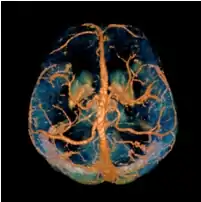

COSMOS solves the inverse problem by oversampling from multiple orientations.[11][12] COSMOS utilizes the fact that the zero cone surface in the Fourier domain is fixed at the magic angle with respect to the B0 field. Therefore, if an object is rotated with respect to the B0 field, then in the object's frame, the B0 field is rotated and thus the cone. Consequently, data that cannot be calculated due to the cone becomes available at the new orientations.

COSMOS assumes a model-free susceptibility distribution and keeps full fidelity to the measured data. This method has been validated extensively in in vitro, ex vivo and phantom experiments. Quantitative susceptibility maps obtained from in vivo human brain imaging also showed high degree of agreement with previous knowledge about brain anatomy. Three orientations are generally required for COSMOS, limiting the practicality for clinical applications. However, it may serve as a reference standard when available for calibrating other techniques.